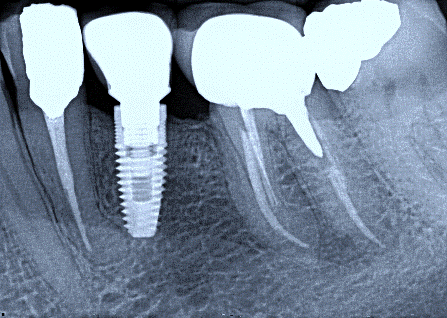

2. (Select ONE OR MORE correct answers)

What observation(s) can be made for tooth 4.7?